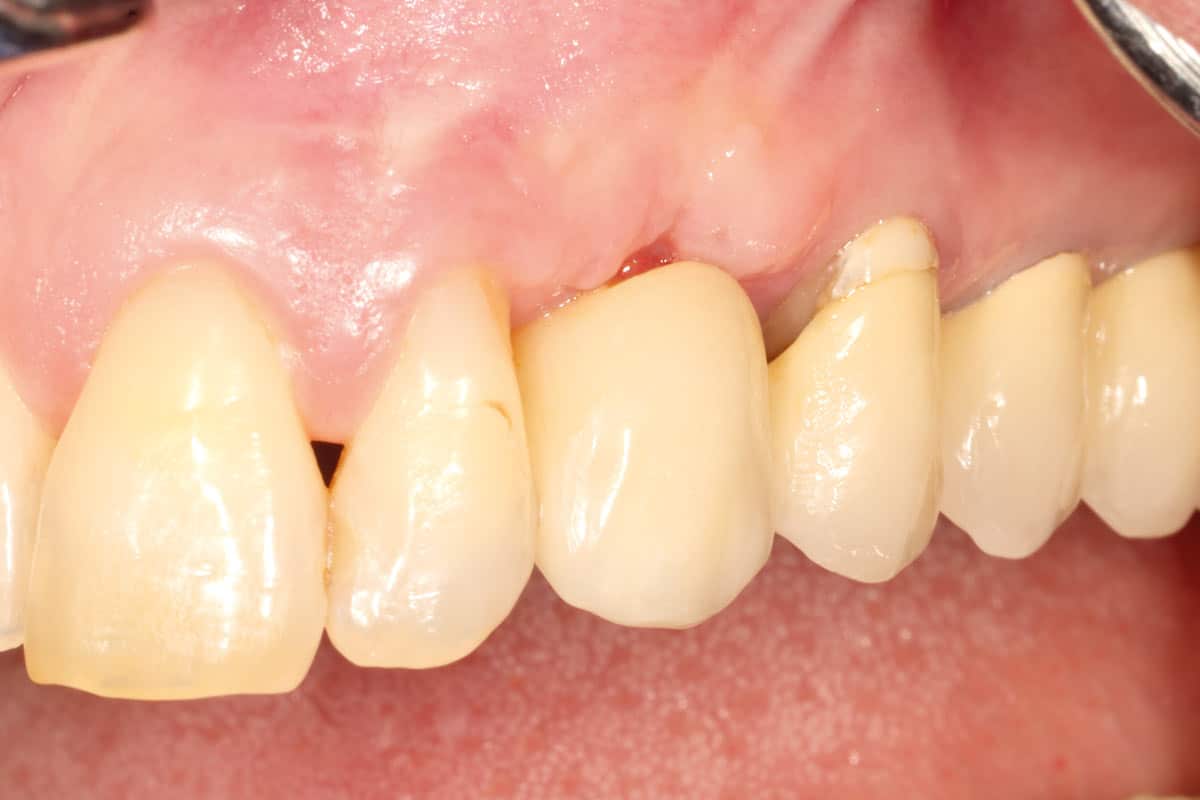

A patient presented with a peri-implant bone defect characterized by bone resorption compromising the stability and long-term prognosis of the implant. To re-establish sufficient bone volume and ensure implant longevity, a regenerative surgical intervention was performed using a guided bone regeneration (GBR) approach. The treatment featured cerabone® plus for grafting, complemented by the Shield Technique using fully resorbable magnesium-based NOVAMag® SHIELD to guide bone regeneration.

At the 6-month follow-up, clinical and radiographic evaluations demonstrated pronounced new bone formation and favourable soft tissue integration, indicating successful regenerative outcomes. By the 12-month follow-up, bone regeneration had advanced even further, and implant stability was significantly strengthened, confirming the procedure’s lasting success. A CBCT scan at 6 months revealed promising results, which were even more striking at the 12-month mark, demonstrating optimal bone integration and implant stability.